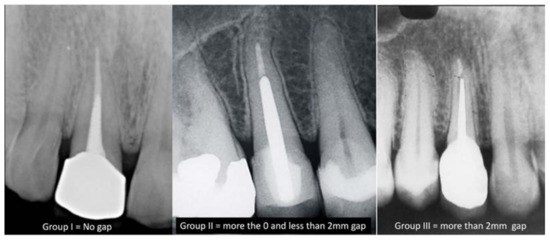

- Group I: no gap between the cemented post and the gutta-percha.

- Group II: a gap of more than 0 but less than 2 mm between the gutta-percha and the post.

- Group III: a gap of more than 2 mm between the gutta-percha and the post.